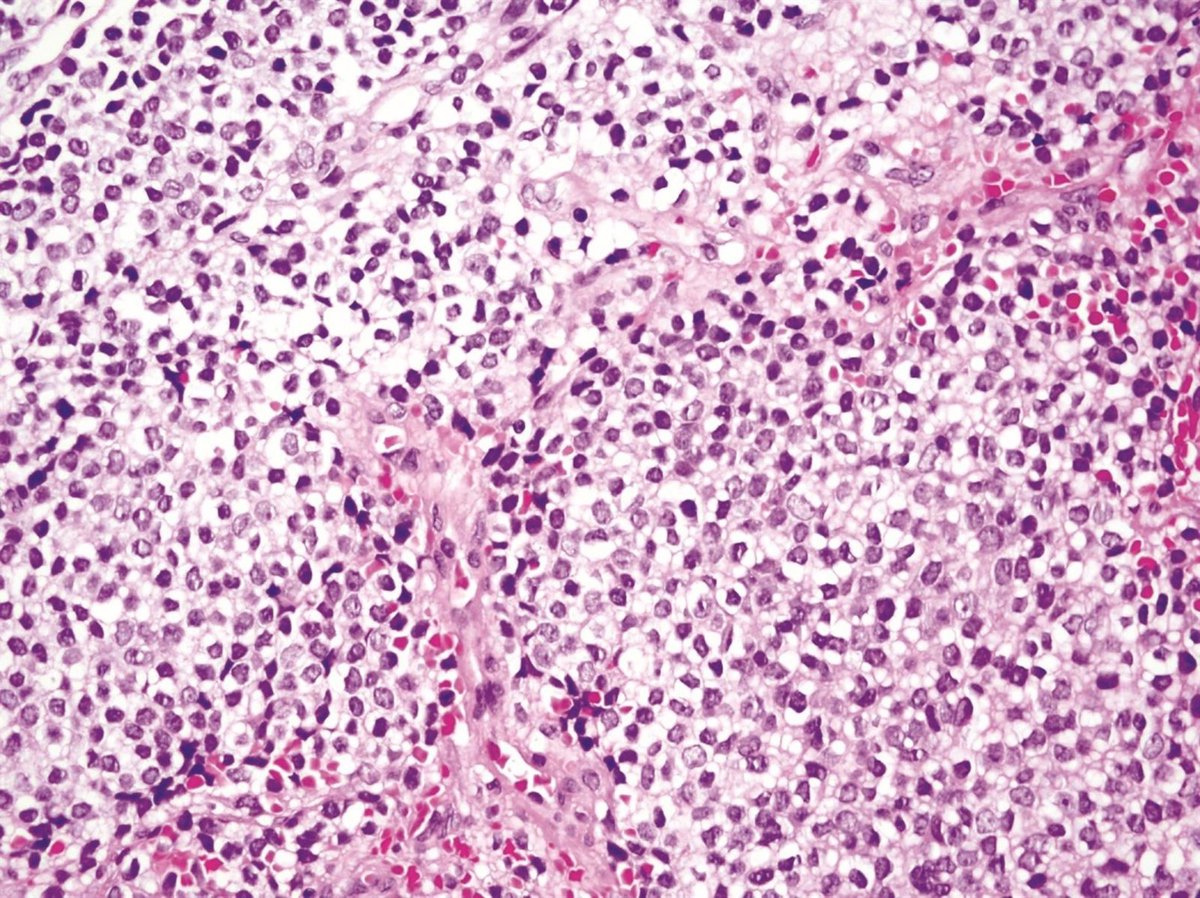

Sarcoma de Ewing.

Sarcoma de Ewing. - UNIVERSIDAD DE SEVILLA

Un equipo del Instituto de Biomedicina de Sevilla (IBiS) ha identificado un nuevo mecanismo molecular que podría explicar la elevada sensibilidad del sarcoma de Ewing --un tumor óseo agresivo que afecta principalmente a niños y adolescentes-- a determinados fármacos quimioterápicos, como el irinotecán, según un estudio publicado en la revista Oncogene. Los investigadores han señalado que estos hallazgos podrían abrir la puerta a estrategias "más personalizadas y eficaces" para el tratamiento de este tipo de cáncer.

La entidad ha explicado que el sarcoma de Ewing está caracterizado por una alteración genética muy específica: la fusión de los genes Ewsr1 y FLI1, que da lugar a una proteína quimérica oncogénica denominada EWS::FLI1. Esta fusión, además de iniciar y sostener el crecimiento tumoral, altera procesos celulares esenciales.